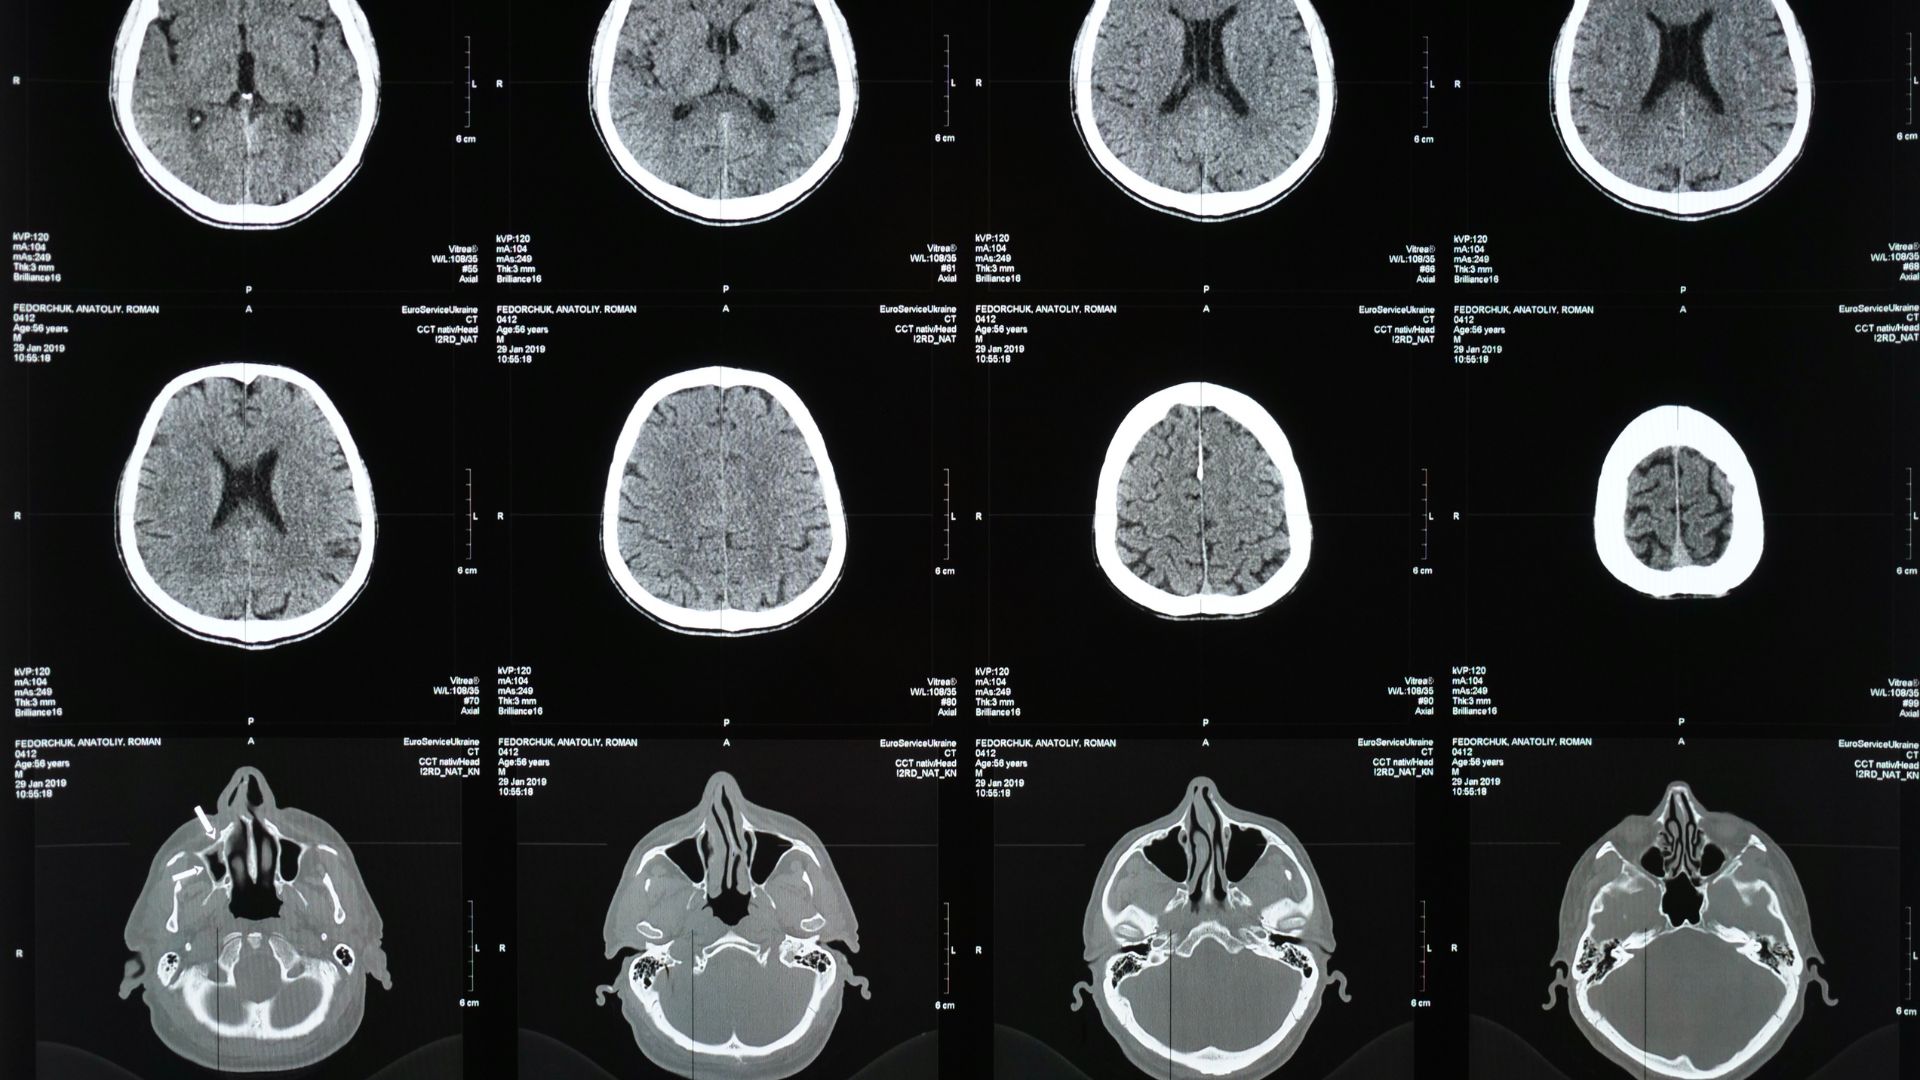

Khi đến bệnh viện, đội ngũ cấp cứu sẽ xem xét các triệu chứng và hoàn thành khám thực thể. Các xét nghiệm giúp bác sĩ xác định loại tai biến mạch máu não đang xảy ra và đưa ra phương pháp điều trị tốt nhất. Các phương pháp xét nghiệm và chẩn đoán có thể bao gồm:

- Chụp CT scan hoặc MRI scan: Cung cấp hình ảnh chi tiết của não và động mạch.